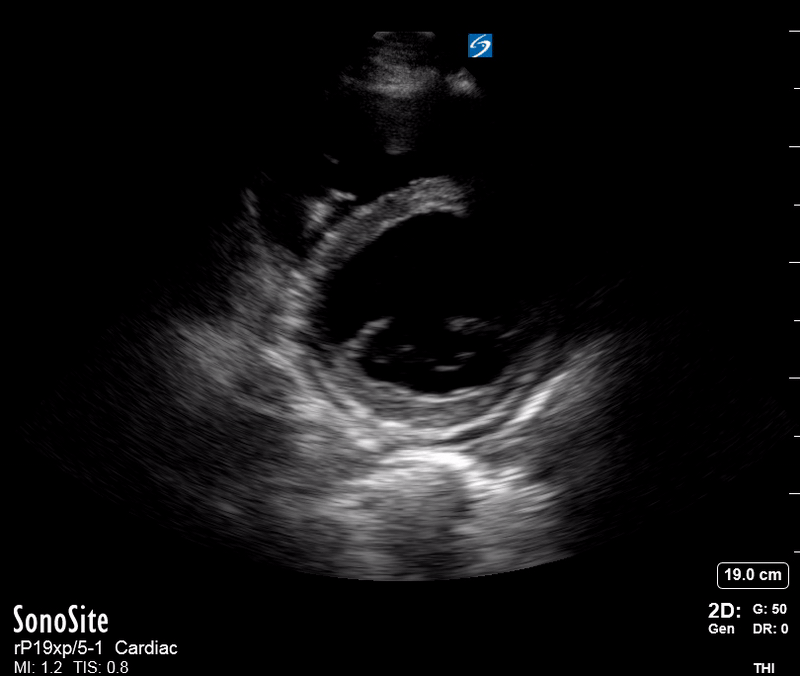

Effusion: is there a pericardial or pleural effusion?

Pericardial effusion is a continuum and can potentially evolve into haemodynamic collapse. Tamponade physiology is detectable earlier with ultrasound than with traditional physical examination, and it has been demonstrated that PoCUS improves mortality in penetrating cardiac trauma. Timely and accurate diagnosis is, therefore, vital.

THE VIEWS

The subxiphoid view is the most reliable for detecting pericardial effusion. Still, it is ideal to obtain different views not to miss a focal effusion as small amounts of fluid can lead to tamponade physiology. Tamponade does not link strictly to the size of the effusion, but correlates more with the speed of onset, causes, and haemodynamic effects.

PITFALLS & PLEURAL EFFUSIONS

A common error is to confuse a pericardial fat pad with effusion. Fatty tissue has a heterogeneous echotexture, moving in coordination with the myocardium, and it cannot be tracked around the heart, especially posteriorly and to the apex. Another pitfall is misinterpreting a pleural effusion as a pericardial effusion. However, they can be differentiated by their relationship to the descending aorta. Pericardial effusion may be seen between the aorta and the LV free wall, whereas pleural effusions are posterior to the descending aorta. Lastly, other causes, namely hypovolaemia and large pleural effusions, can cause RA and RV collapse.

CARDIAC TAMPONADE

Progressively rising pressure translates into evolving tamponade, and this accompanies a series of ultrasound findings:

Initially, the RA collapses during ventricular systole (closed AV valves).

Followed by RV collapse in ventricular diastole (open AV valves).

Ultimately leading to LV collapse.

In addition, the presence of a non-collapsible, plethoric IVC is one of the most sensitive signs of tamponade, and a finding easy to visualise. Conversely, a pericardial effusion in a haemodynamically stable patient with a collapsible IVC is unlikely to represent tamponade.